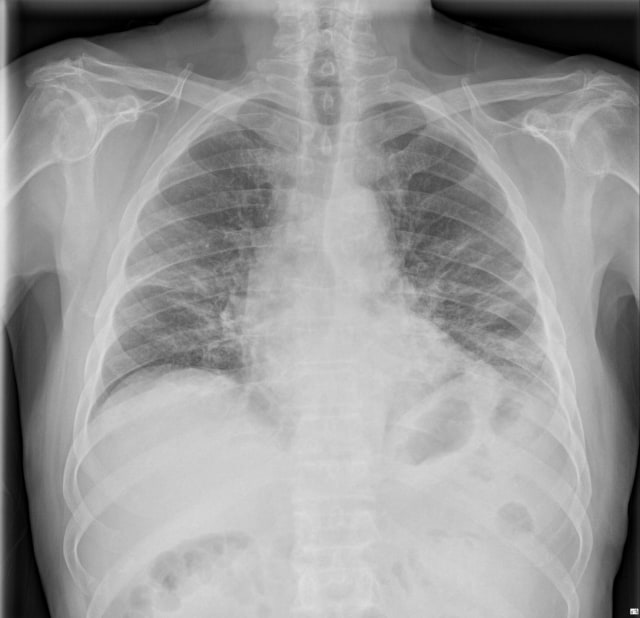

Spanyol menjadi salah satu negara dengan pertumbuhan pasien COVID-19 yang tinggi. Baru-baru ini akun Twitter @ChestImaging mengunggah sejumlah foto hasil rontgen pasien positif corona.

Foto-foto tersebut berasal dari hasil pemeriksaan pasien di sebuah rumah sakit di Spanyol. Berikut gambar-gambarnya: